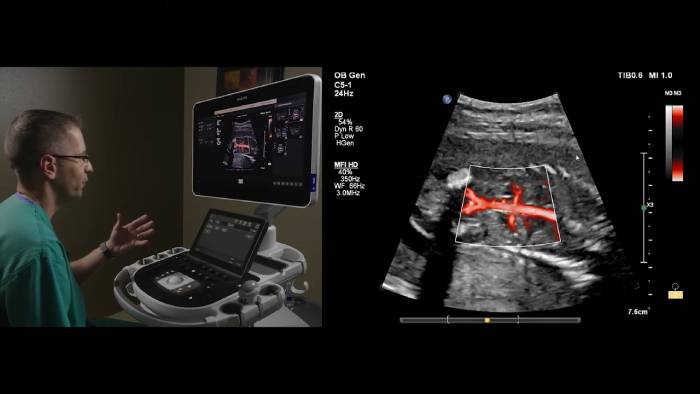

Microflow Imaging High Definition (MFI HD) da Philips

Neste vídeo, o Dr. Michael Ruma, da Perinatal Associates, New Mexico, explora a utilização do MFI HD da Philips em aplicações fetais com os transdutores eL18-4 e C5-1.